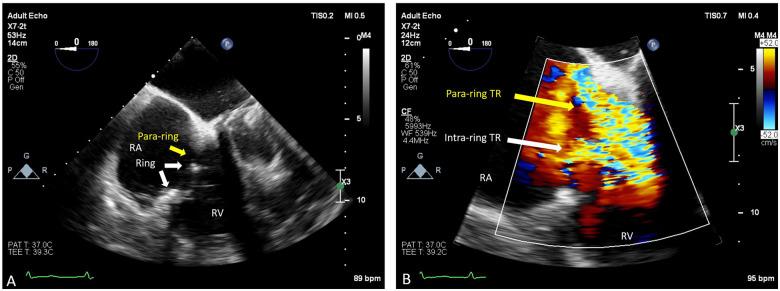

A 52-year-old female was diagnosed with severe rheumatic valvular heart disease. The patient underwent mechanical aortic and mitral valve replacement. Additionally, tricuspid repair was performed using a semi-rigid annuloplasty ring (28 mm Edwards Physio Tricuspid). Within 2 years, the patient developed recurrent, isolated severe symptomatic TR, with progressive right ventricular dilatation. The patient was considered prohibitive risk for redo surgery and unsuitable for cardiac transplantation. She underwent percutaneous valve-in-ring transcatheter heart valve (THV) implantation using a 29 mm Sapien S3 (Edwards Lifesciences, CA, USA) valve. Persistent severe residual para-ring TR warranted a further procedure to deploy vascular plugs, significantly reducing the TR to a mild jet with symptomatic improvement.

Valve-in-ring THV implantation for failed surgical tricuspid annuloplasty repair is a rare procedure reserved for symptomatic patients at high or prohibitive risk for reoperation. Significant residual TR is a commonly encountered problem with incomplete annuloplasty rings following valve-in-ring procedures and may occur either intra-ring between the THV and the ring or para-ring. Implantation of vascular occlusion devices can be used to successfully treat residual TR at either location with good outcomes at 6-month follow-up. Further work is required to determine the longevity of this treatment.